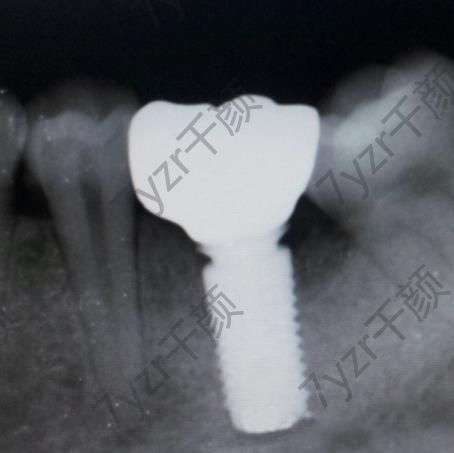

時(shí)間過(guò)得實(shí)在是太快了。我感覺(jué)這三個(gè)月要比我想象中過(guò)得快一些,也有可能是因?yàn)檫@一段時(shí)間工作比較忙的原因吧。沒(méi)有時(shí)間去瞎想,所以感覺(jué)時(shí)間就過(guò)的更快了,現(xiàn)在的我已經(jīng)裝上牙冠了??傮w來(lái)說(shuō),這種感覺(jué)還是挺不錯(cuò)的,畢竟已經(jīng)沒(méi)有了那個(gè)牙洞?,F(xiàn)在的我因?yàn)閯倓傃b上牙冠沒(méi)有多長(zhǎng)時(shí)間,所以現(xiàn)在還在忌口,醫(yī)生說(shuō)再堅(jiān)持一段時(shí)間就什么東西都可以吃了。

因?yàn)槲曳N植牙到這件事情沒(méi)有告訴我的媽媽。前幾天放假回家的時(shí)候,我還特意張開(kāi)嘴巴讓我他看我嘴巴里有什么變化。媽媽一眼就看出來(lái),我之前的那個(gè)牙洞沒(méi)有了,還問(wèn)我那個(gè)地方裝的是什么東西,我告訴她是一顆新的牙齒,媽媽還特別的疑問(wèn)說(shuō),這么大了,怎么可能長(zhǎng)出新的牙齒?我告訴他,我是去口腔醫(yī)院種植的牙齒,媽媽還特意觀察了一下,不仔細(xì)看的話,根本看不出來(lái)是假的。